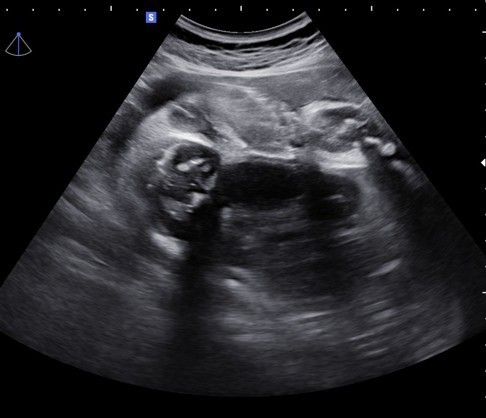

อันนี้คือหว่างขาใช่มั้ยคะะ ดูไม่ออก

เพศหญิงใช่มั้ย แม่อยากมั่นใจจจจ😁

แบบนี้ผญไหมค่ะ

น่าจะญ.นะคะแม่

ญ ค่ะแม่